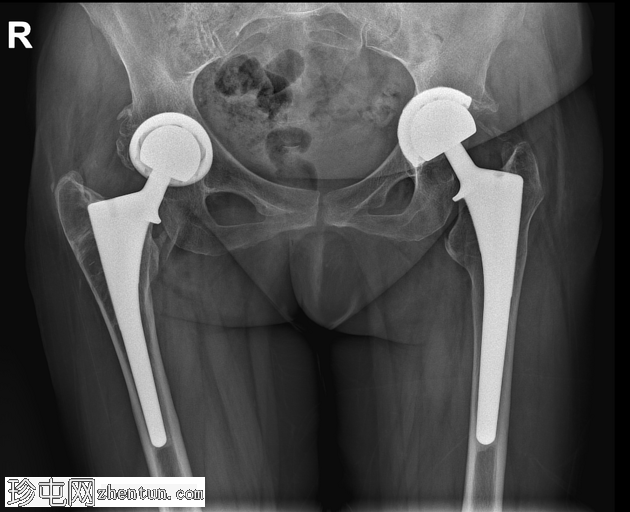

矢状位片

平扫

左侧全髋关节置换术。大转子基底部可见轻微移位的假体周围骨折。

大转子滑囊积液,可见脂肪-液体平面。

股骨大转子滑囊扩张并伴有脂肪-液体平面提示创伤性脂肪血肿。